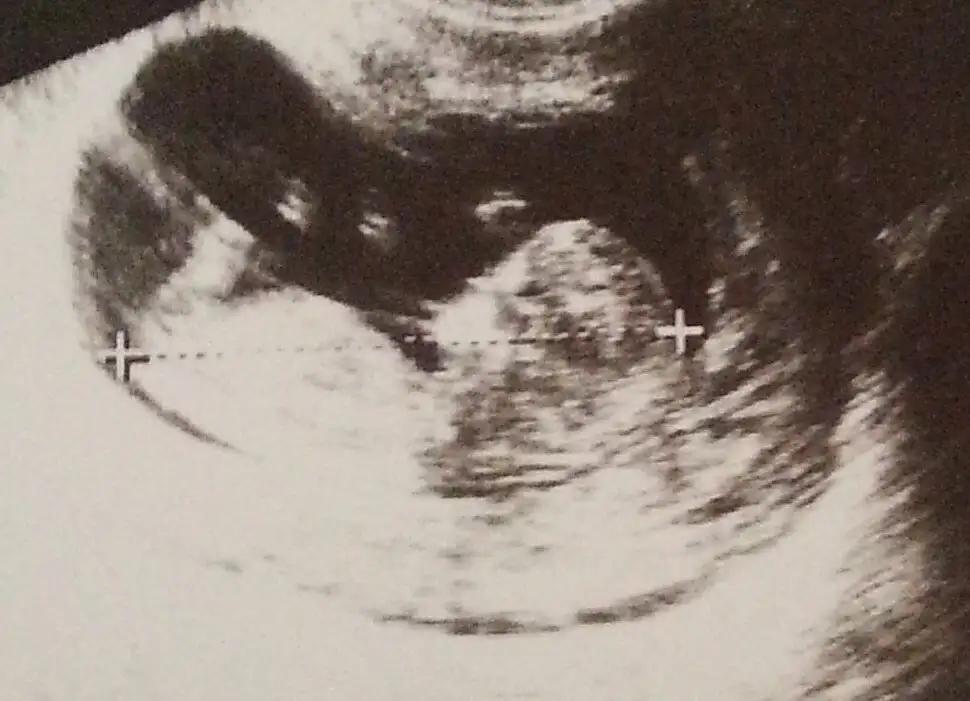

Kızlar biri 9 haftalik biri 12 haftalık cinsiyet ile dusuncelerinizi yazarsaniz sevinirim...

Eklentiler

• 20150322_122431.webp

20150322_122431.webp

15,7 KB · Görüntüleme: 146

• 20150322_132905.webp

20150322_132905.webp

13,2 KB · Görüntüleme: 142

Kızlar biri 9 haftalik biri 12 haftalık cinsiyet ile dusuncelerinizi yazarsaniz seviniri/QUOTE]

Canim 9 haftalik resimde kesenin soluna yakin yani erkek ama 12 haftalik resimdede hic cikinti yok kiz gibu yatiyo .. baska foto yokmu ? Doktor hicmi yorum yaomadi? Son fotoya yorum yaparsam kiz bence...

Valla hiç birşey söylemedi. Gözükmüyor daha belli olmaz 15 16 haftalarda anlaşılır dedi.12 haftalarda öğrenenler cok şanslı.ben de çok baktım ama çıkaramadım bişey.